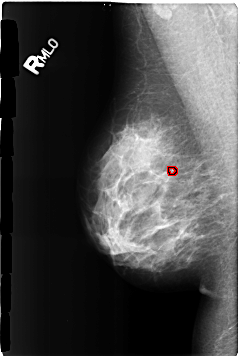

B_3169_1.RIGHT_MLO

RIGHT_MLO LINES 4624 PIXELS_PER_LINE 3112 BITS_PER_PIXEL 12 RESOLUTION 50 OVERLAY

FILE: B_3169_1.RIGHT_MLO.OVERLAY

TOTAL_ABNORMALITIES 1

ABNORMALITY 1

LESION_TYPE CALCIFICATION TYPE LUCENT_CENTERED DISTRIBUTION N/A

ASSESSMENT 2

SUBTLETY 3

PATHOLOGY BENIGN

TOTAL_OUTLINES 1

BOUNDARY